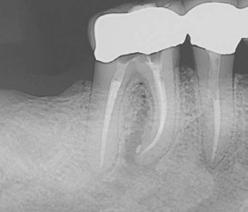

Clinical case performed by Dr. Benedict Bachstein (Figures 1-3)

The patient was diagnosed with irreversible pulpitis in tooth number 14, which presented multiple canals with highly complex anatomies. All canals were instrumented to 25/.04 and cleaned with Odne®Clean following the recommended clinical protocol. The use of Odne®Clean enabled the identification of five canal orifices and clearing of apical deltas.

Clinical case performed by Dr. Brett Gilbert (Figures 4 and 5)

In this case, Dr. Gilbert was initially unable to locate the MB2 canal, despite thorough attempts using ultrasonic and a microscope. After performing the irrigation protocol with Odne®Clean, the MB2 became visible. Following activation, the filling material extended completely through the MB2.

Clinical case performed by Dr. Sameer Jain (Figures 6 and 7)

The RCT involved a deep split tri-furcated premolar. Use of Odne®Clean enabled access to the advanced canal anatomy.